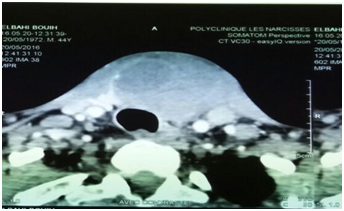

We report the case of the 44-year-old patient, who for 5 years showed a cervical swelling gradually increasing in volume and subsequently compressive, with an alteration in the general condition, with cervical ultrasound completed by cervical CT In preoperative procedures: nodular heterogeneous hypoechoic goitre of 38* 49* 4 mm with calcifications 4C(according to the 2015 criteria of the American Cancer Society) , with compression and repression of left jugular carotid and trachea, absence of cervical adenopathies (Figure 1). The gesture consisted of a total thyroidectomy, the anatomopathological study showed a malignant proliferation, little differentiated and infiltrating, presence of vascular emboli, peri-nervous entrapment and capsular effraction, the immunohistochemical study showed a carcinoma Little differentiated and infiltrating, classified pT3NxMx, the evolution was marked at day 5 of postoperative by recurrence of the cervical swelling with compressive signs to the type of dysphagia and dysphonia, the clinical examination finds: a firm anterior cervical mass painful An ultrasound was performed in which the bulk of the bilateral clavicular and bilateral cerebral regions that could be associated with lymphadenopathy were examined, a cervical computed tomography (Figure 2) had shown a large tumorous process from the cervico-mediastinal orifice to the hyoid bone infiltrating the soft tissue without adenopathy, after three days of development the patient died as a result of Complications and tumor hemorrhage.

Figure 1 CT scan (before surgery) showing a voluminous cervical tumor process.